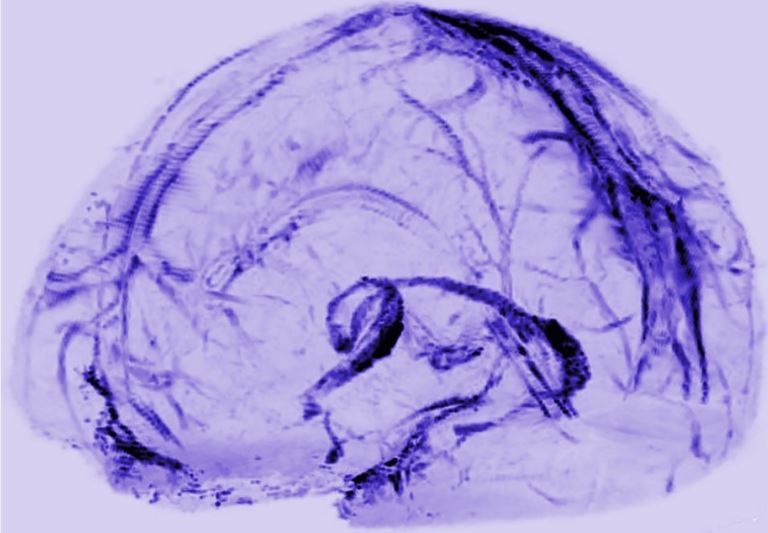

Human and nonhuman primate meninges harbor lymphatic vessels that can be visualized noninvasively by MRI Oct 2017

Martina Absinta Seung-Kwon Ha Govind Nair Pascal Sati Nicholas J Luciano Maryknoll Palisoc *Antoine Louveau Kareem A Zaghloul Stefania Pittaluga Jonathan Kipnis Daniel S Reich Is a corresponding author expand author list see all

National Institute of Neurological Disorders and Stroke, National Institutes of Health, United States National Cancer Institute, National Institutes of Health, United States University of Virginia, United States